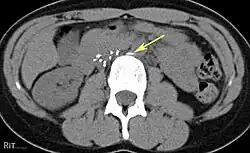

Abdominal radiograph shows that one of the legs (arrows) of the IVC filter is pointed away from the expected IVC lumen.

Axial CT image confirms that one of the legs (arrow) of the IVC filter has migrated out of the IVC wall into an adjacent tissue.